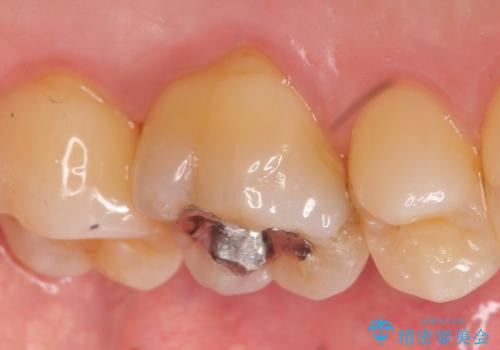

- ものを咬むと痛むので診て欲しいといらっしゃった方の症例です。

数年前に他院にて虫歯治療後しばらく痛みがあったが、やがて治まった。その後何事もなかったが、数か月前からものを咬むと痛むようになったとのこと。

検査の結果歯の神経が死んでいたため根管治療を施し、症状が治まったのを確認後オールセラミッククラウンによる補綴を行いました。